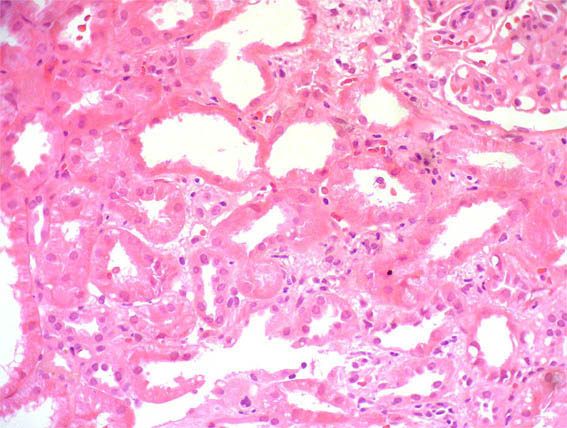

Figure 10. H&E, X200.